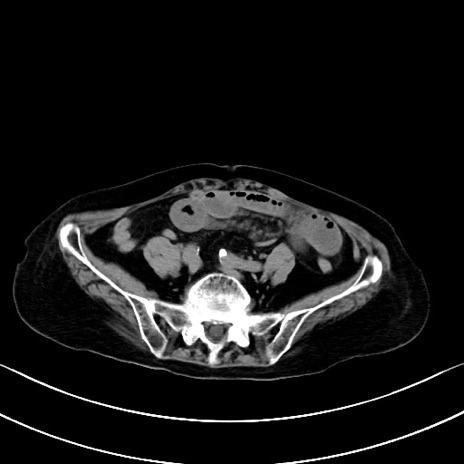

横断像

他院CT